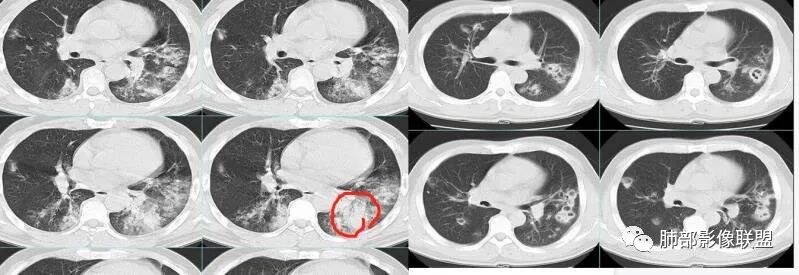

治疗后复查

今天的病例复查很符合金葡菌

第一次不典型

左下肺的囊腔呈簇状分布

这个区域应该是外侧最重的,但是没有看到空洞。二元论也可以,单纯从影像看金葡也不一定都是小叶性改变的,肺泡性改变也可以,从病史看,可能病毒合并金葡。

金葡不会等到半个月还是斑片状影的,金葡变化很快,一般是按天、甚至按小时计算的。

这个炎症当时也考虑过金葡,但是病史是半个月,所以就排除了,病史不符合金葡

这个病史发热三天,胸痛可能是后面金葡引起的,这些不一定是金葡,可能就有基础疾病,合并的这个。真正的病史就是金葡引起,病史就发热三天,近期加重,这三天就是金葡的改变。

就是说这个基础病变不知道是什么,肯定有基础病变,不然不符合,因为前上个星期才去讲这个金葡的,当时一看,这个斑片斑片确实有金葡的一些特点存在,支气管壁有增厚。

那我当时很诧异的就是这个,刚才说这个感染没有问题,恶性特征真没有,不符合,看到这个周围有一定的修复的迹象,这个特别诧异,怎么会是这样改变。

怀疑这个可能是在治疗过程中,改变了影像学表现。

这是气道早期金葡菌的特点